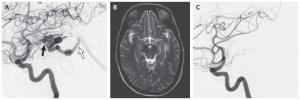

ĐIỀU TRỊ DỊ DẠNG ĐỘNG TĨNH MẠCH NÃO

Xạ phẫu (stereotactic radiosurgery)

Xạ phẫu là phương pháp điều trị đã được nghiên cứu rất nhiều đối với các AVM12. Các kỹ thuật như gamma knife, cyber knife, proton beam, hội tụ, đưa một liều chiếu xạ lớn đến khối dị dạng, nhằm kích hoạt quá trình tạo xơ của mạch máu và làm huyết khối tắc mạch của tổn thương.

Dị dạng động tĩnh mạch não (AVM) là bất thường bẩm sinh mạch máu trong não, xuất hiện do quá trình phát triển bất thường của hệ thống mạch máu, tạo ra sự thông thương trực tiếp giữa các động mạch não với tĩnh mạch não.